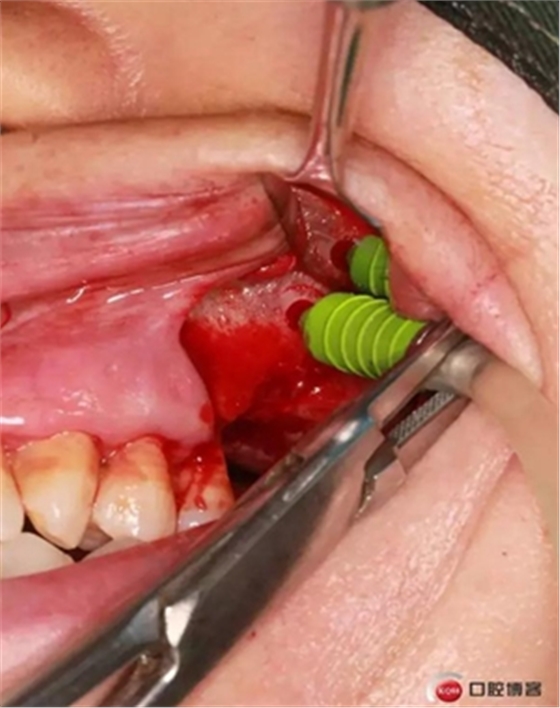

大家好,我是梁老師的助理小依。由于梁老師每天手術(shù)檔期安排較滿,加上經(jīng)常出差講課,沒有時間整理病例 。為了方便大家更及時的了解梁老師最新手術(shù)動態(tài),以后將由我為大家整理并推送梁老師最新經(jīng)典案例。案例文字旁白少,但圖片會盡量完整展示手術(shù)全過程,供大家學(xué)習(xí)參考。有任何問題,可以留言,梁老師會親自為大家解答。感謝大家對梁老師的支持和關(guān)注!